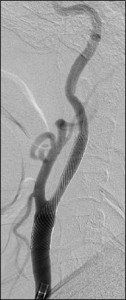

当科で治療した年々大きくなった大型脳底動脈瘤の3次元脳血管撮影像です。脳動脈瘤と周囲の血管の状態が非常によく分かるため、術前に十分な検討が可能でした。

正常の脳底動脈の血流は維持されている。